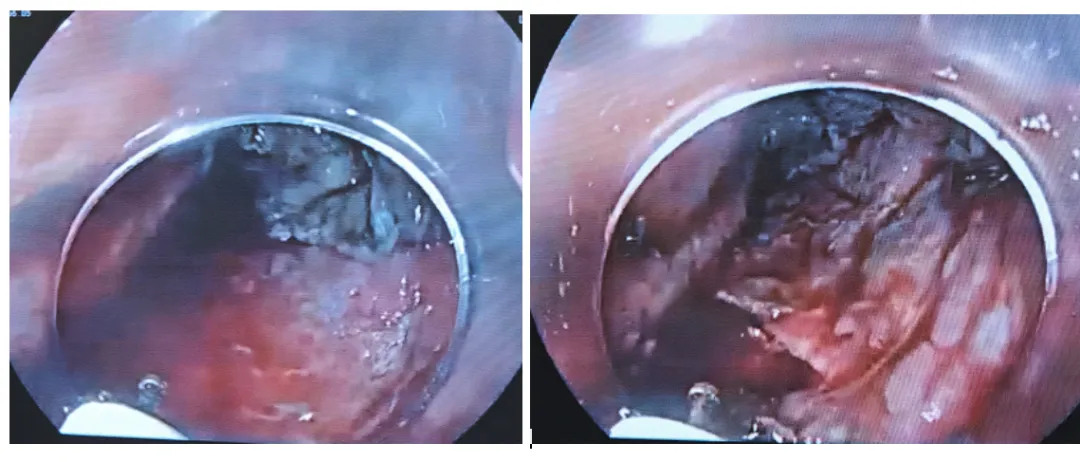

10:05-14当剥离到困难时,有时也会用牙线或圈套器或“O”型圈内牵引,用“口袋法”自身牵引也可以。有些地方纤维化非常明显,现在是利用重力往下牵引剥离

10:41这个病灶纤维化很明显,粘膜下注射水垫只给我们切一刀,水垫就消失了。10:44遇到血管,先裸化,用热止血钳电凝再切断。

10:53左侧这部分粘连比较严重,这里好几个地方都是偏低位,可能需要改变体位或用到牵引

10:56患者是左侧卧位,现在换成平卧位,病灶还是在低位,可能还是需要用到牵引来辅助

10:59把病灶往下推利用重力牵引。

准备进圈套器牵引,用钛夹带圈套器进去夹住病灶口侧拉起来,可拉,可推(牙线太细,没有圈套器那么好效果)

11:06边补水边剥离11:08病灶切下来了。